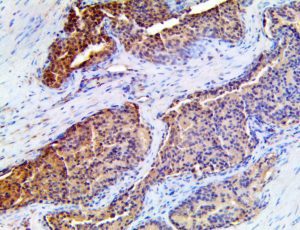

The first cytokines released are interleukin 1β (IL-1β) and tumor necrosis factor-α (TNF-α), which attract a variety of circulating white blood cells (WBCs) to the infection site, including neutrophils, monocytes, macrophages, and natural killer (NK) cells. This response, along with the antipathogenic chemicals released by these cells (i.e., complement), comprise the innate immune response. These cells directly attack the invading pathogen and also release additional cytokines, chief among them interleukin-1 and 6 (IL-6). IL-6 is essential for invoking the adaptive immune response, which calls T-cells, B-cells, and T helper (Th) cells to the infection site. IL-6 also stimulates further recruitment, proliferation and activation of macrophages.

It is the ICU physician who is most likely to witness one of the deadliest manifestations of the abnormal immunological response, the cytokine storm syndrome (CSS). This response is also referred to by some as the cytokine release syndrome (CRS). CSS is characterized by continuous activation and expansion of macrophage and lymphocyte populations, which secrete large amounts of cytokines, causing the cytokine storm. This massive cytokine release is akin to hemophagocytic lymphohistiocytosis (HLH) disease, a syndrome characterized by initial unchecked and persistent activation of cytotoxic T lymphocytes and NK cells.